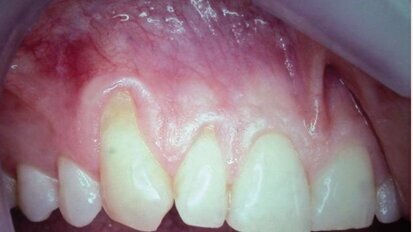

Rendre des facettes unitaires si naturelles qu'elles soient indétectables

Comme les patients vieillissent, les dents antérieures présentent souvent de l'usure, de l'effritement et de la décoloration. Ces ...